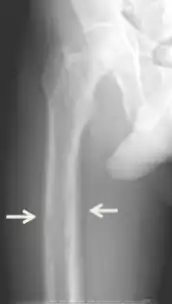

El diagnóstico incluye análisis tanto clínicas como de laboratorio. Las investigaciones radiológicas buscan signos de pérdida de hueso en manos y pelvis, rasgo característico hiperparatiroidismo terciario.[8] Otro examen clínico puede incluir la clasificación de la debilidad muscular, que se realiza pidiendo al paciente que se ponga de pie desde una posición sentada con las manos cruzadas sobre el pecho.[4] Los análisis de laboratorio incluyen determinación del nivel de calcio de sangre y de fosfatasa alcalina, los cuales están siempre aumentados en el hiperparatiroidismo terciario. Otros resultados comunes de laboratorio incluirían niveles disminuidos de vitamina D, hormona paratiroidea elevada de sangre elevada e hiperfosfatemia.[9][1]